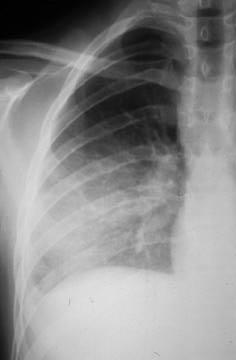

Consolidation

opacification with air bronchograms

e.g cancer, pneumonia, haemorrhage, edema